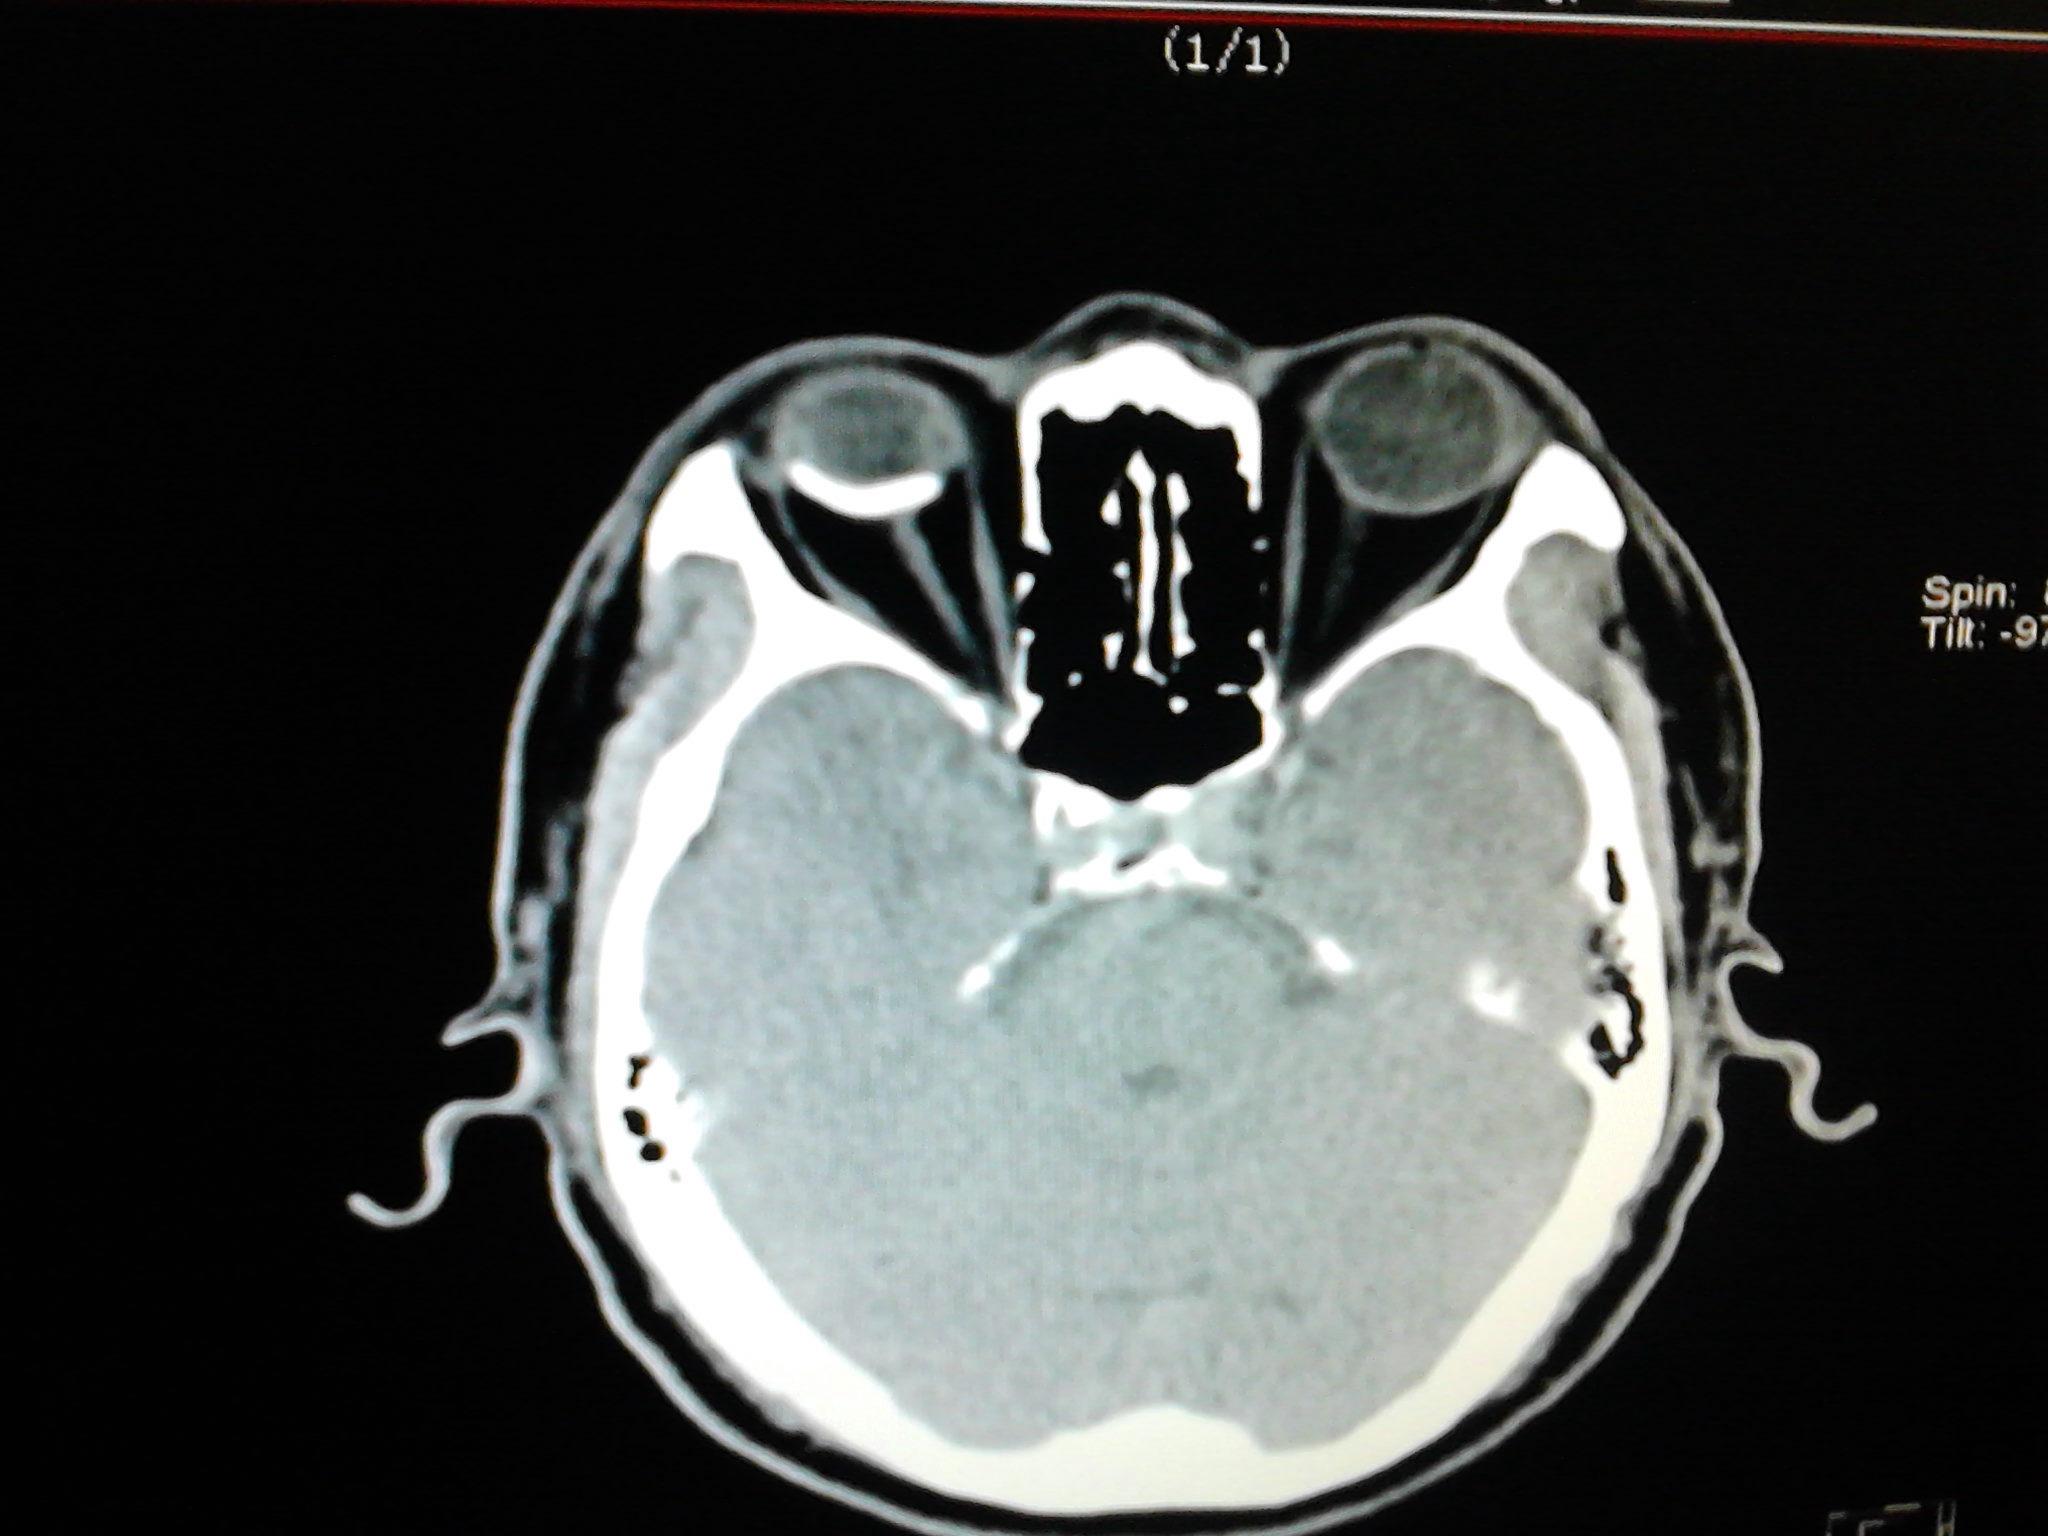

大家都来看看这个眼ct.很少见的

图片尺寸2560x1920